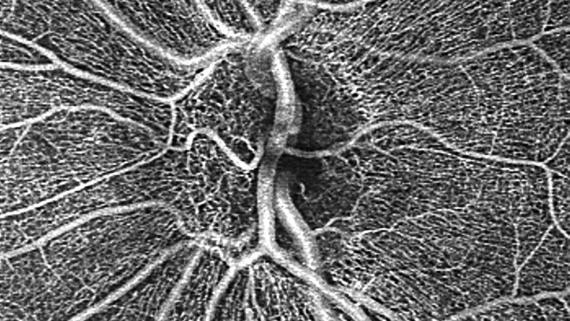

• See wider for a quick vascular assessment

See wider for a quick vascular assessment

Visualização mais ampla para avaliação vascular

O exame OCTA de campo amplo permite a visualização da vascularização e a detecção de doenças que afetam a mácula e a retina periférica, possibilitando uma avaliação vascular rápida e completa.

• 6x6 mm HD AngioPlex OCTA of non-proliferative diabetic retinopathy (NPDR)

6x6 mm HD AngioPlex OCTA of non-proliferative diabetic retinopathy (NPDR).

Image courtesy of Roger Goldberg, MD, Bay Area Retina Associates, United States